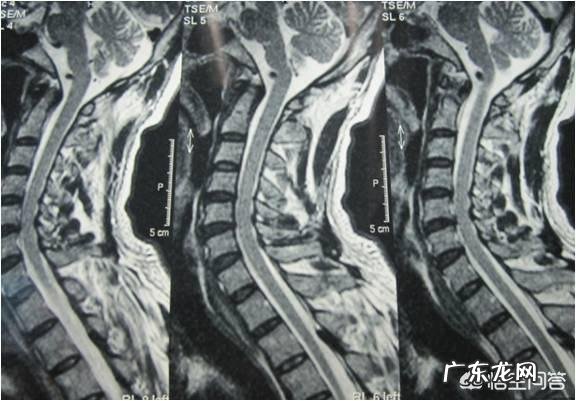

颈椎间盘突出症

也要预防颈椎间盘突出症的发生,矫正探颈的姿势,颈部的前探会增加颈部椎间盘的受力,诱发颈椎间盘突出症,C6~8神经受刺激会造成相应的手部症状,增强颈部肌肉的力量,也可以减小手麻的发生几率 。